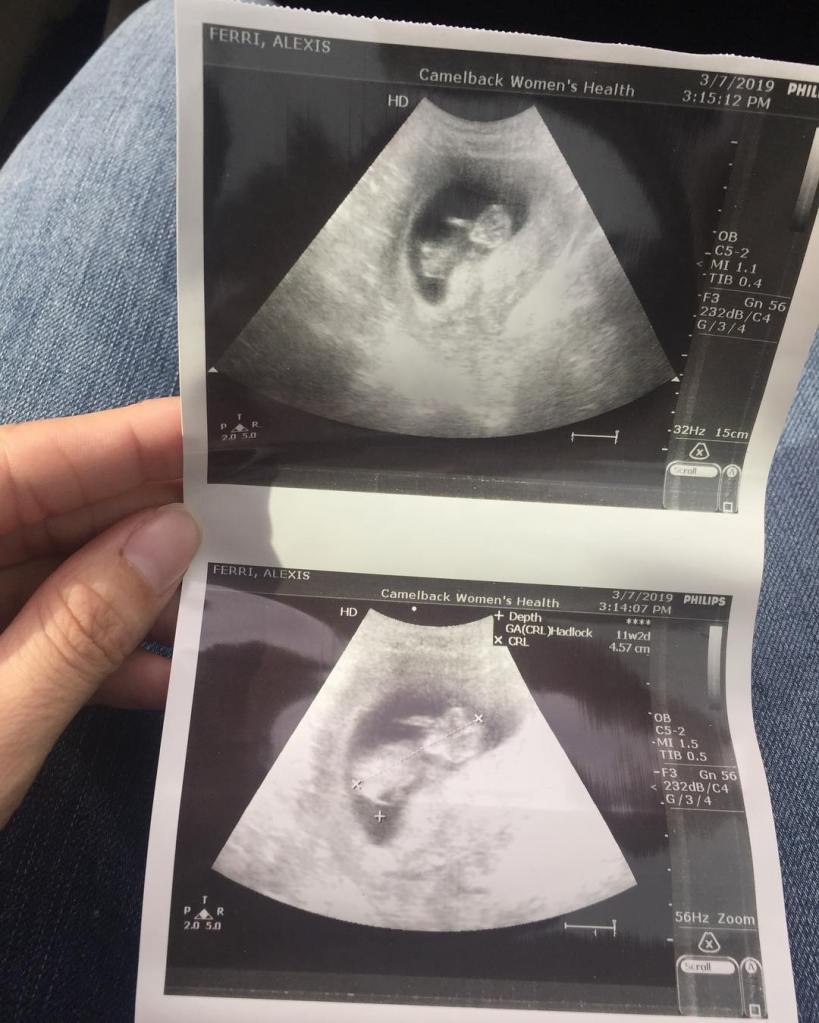

Today we had another check up with my doctor. Whereas the first ultrasound we saw a tiny little speck on the screen, this one revealed a wiggling little somebody, who squirmed when he/she was poked and moved around and even waved to us a little (his/her little hand is raised in the picture).

Based on the size of the baby, my doctor estimated my due date five days behind our calculation, which has changed our due date to September 24th… my birthday.